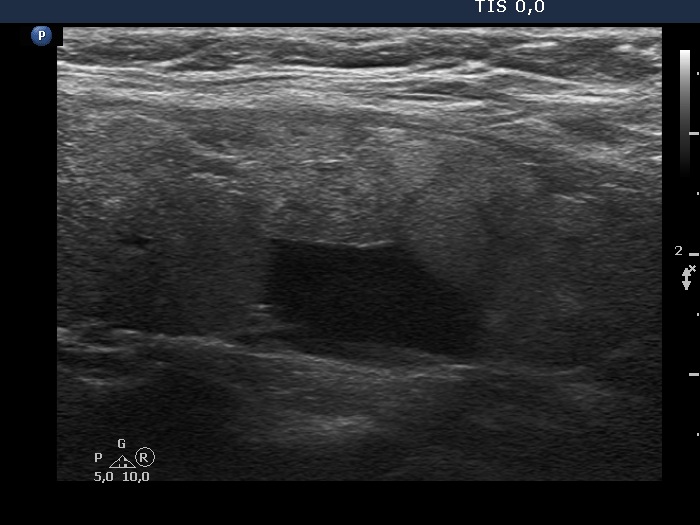

Parathyroid lesions - case 2148 (ultrasonographic picture 8)

Left lobe, another longitudinal view.